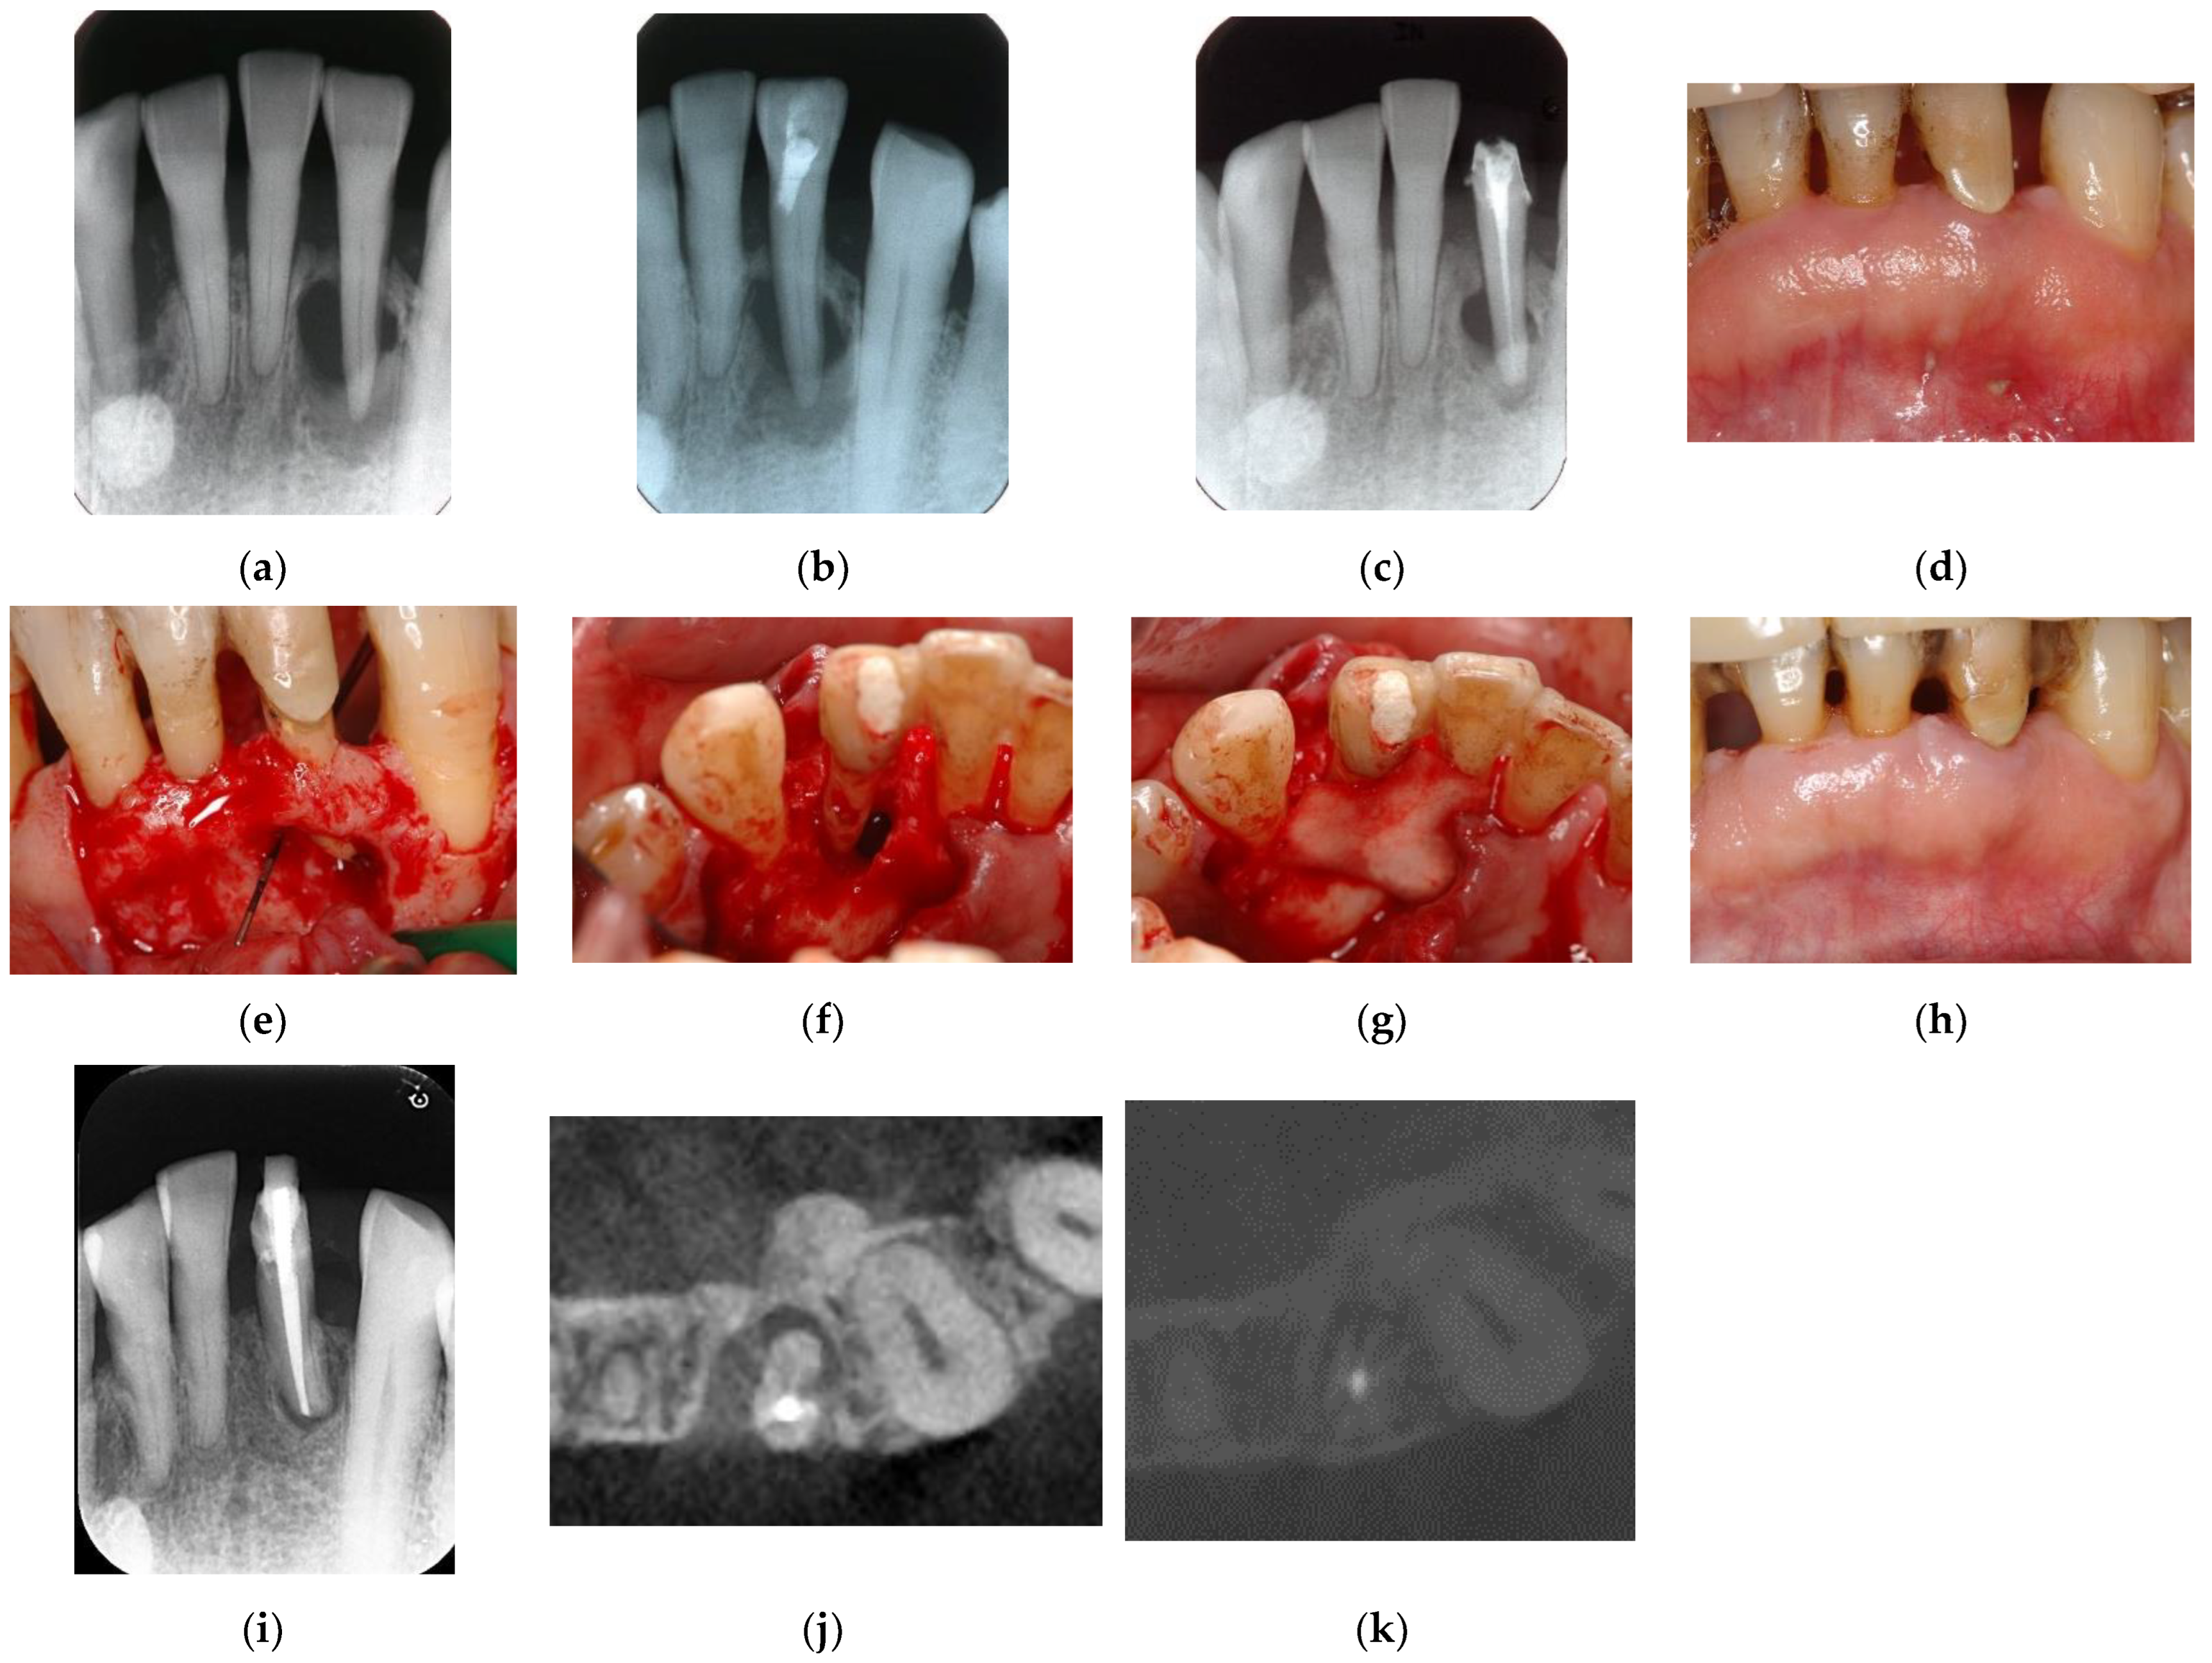

Figure 6. Clinical case 5. Female, age 36 yrs. (a) Intraoral view of the upper left first maxilla at baseline, showing two sinus tracts (arrows). (b) Preoperative periapical radiograph, in which the “bone” defect appeared as a radiolucent area around the MB root. (c) Periapical radiograph after root canal retreatment. (d) View after flap retraction and debriding of the defect, showing two bone defects. (e) GTR treatment with two resorbable membranes. (f) Periapical radiograph after regenerative treatment. (g,h) Preoperative CBCT showing a radiolucent lesion on the periapical and bifurcation areas. (i,j) CBCT findings after endodontic retreatment. (k,l) Follow-up CBCT 10 years after treatment, showing healing of the two bone defects.